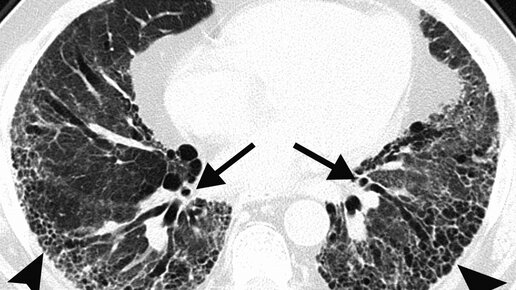

Что такое фиброз легких: причины, симптомы и лечение

Согласно исследованиям регистра пациентов с идиопатическим легочным фиброзом (ИЛФ), в России фиброз легких встречается у 4–7 человек из 100 000. В статье рассказываем о видах, причинах возникновения и симптомах фиброза легких, а также о методах диагностики и лечения этого заболевания. Фиброз легких — это необратимый процесс замещения здоровой ткани легких рубцовой, в результате чего снижается эластичность легких. Так, альвеолы (легочные пузырьки, в которых происходит газообмен) теряют способность нормально расширяться и сокращаться...